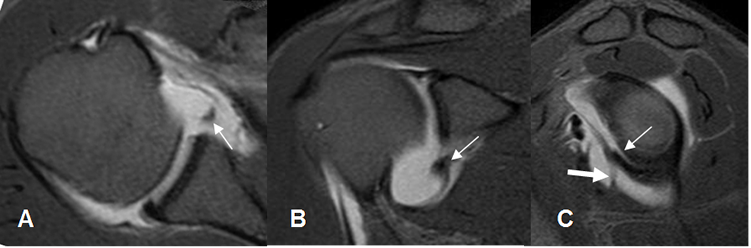

Fig 64. Lesión de Bankart.

A: ArtroRM axial y B: ArtroRM coronal en STIR. Desprendimiento del labrum antero-inferior, por lesión de bankart.

C: ArtroRM sagital en STIR. El desprendimiento del labrum, se presenta sobre la inserción del LGH medio. (Flecha gruesa).